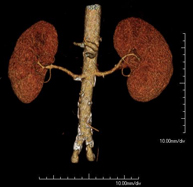

Renal artery CT angiography

A non-invasive diagnostic test that involves studying the renal arteries by obtaining high-definition anatomical images using CT (computed tomography) equipment and iodinated contrast. With the aid of workstations specialised for arterial studies, the image quality supports 2D and 3D reconstructions. This test is recommended, for example, in patients suffering from refractory hypertension that does not respond to processing, in patients with kidney damage in order to obtain a pre-surgical ‘vascular’ map, etc.